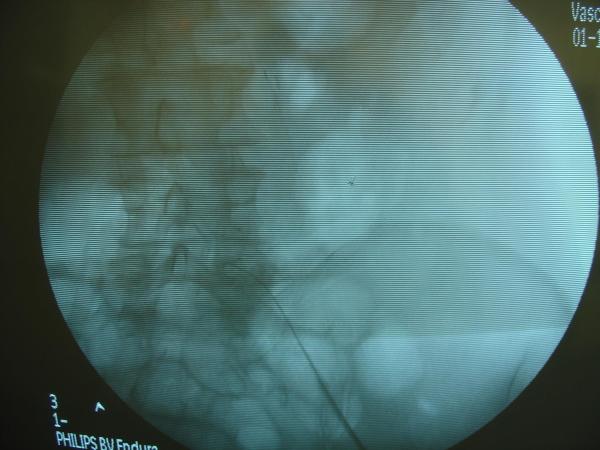

Endovascular repair of anastomotic abdominal aortic aneurysm, after aortobifemoral bypass

Vascular Clinic, Naval and Veterans Hospital of Athens

AVEM2009-Thessaloniki